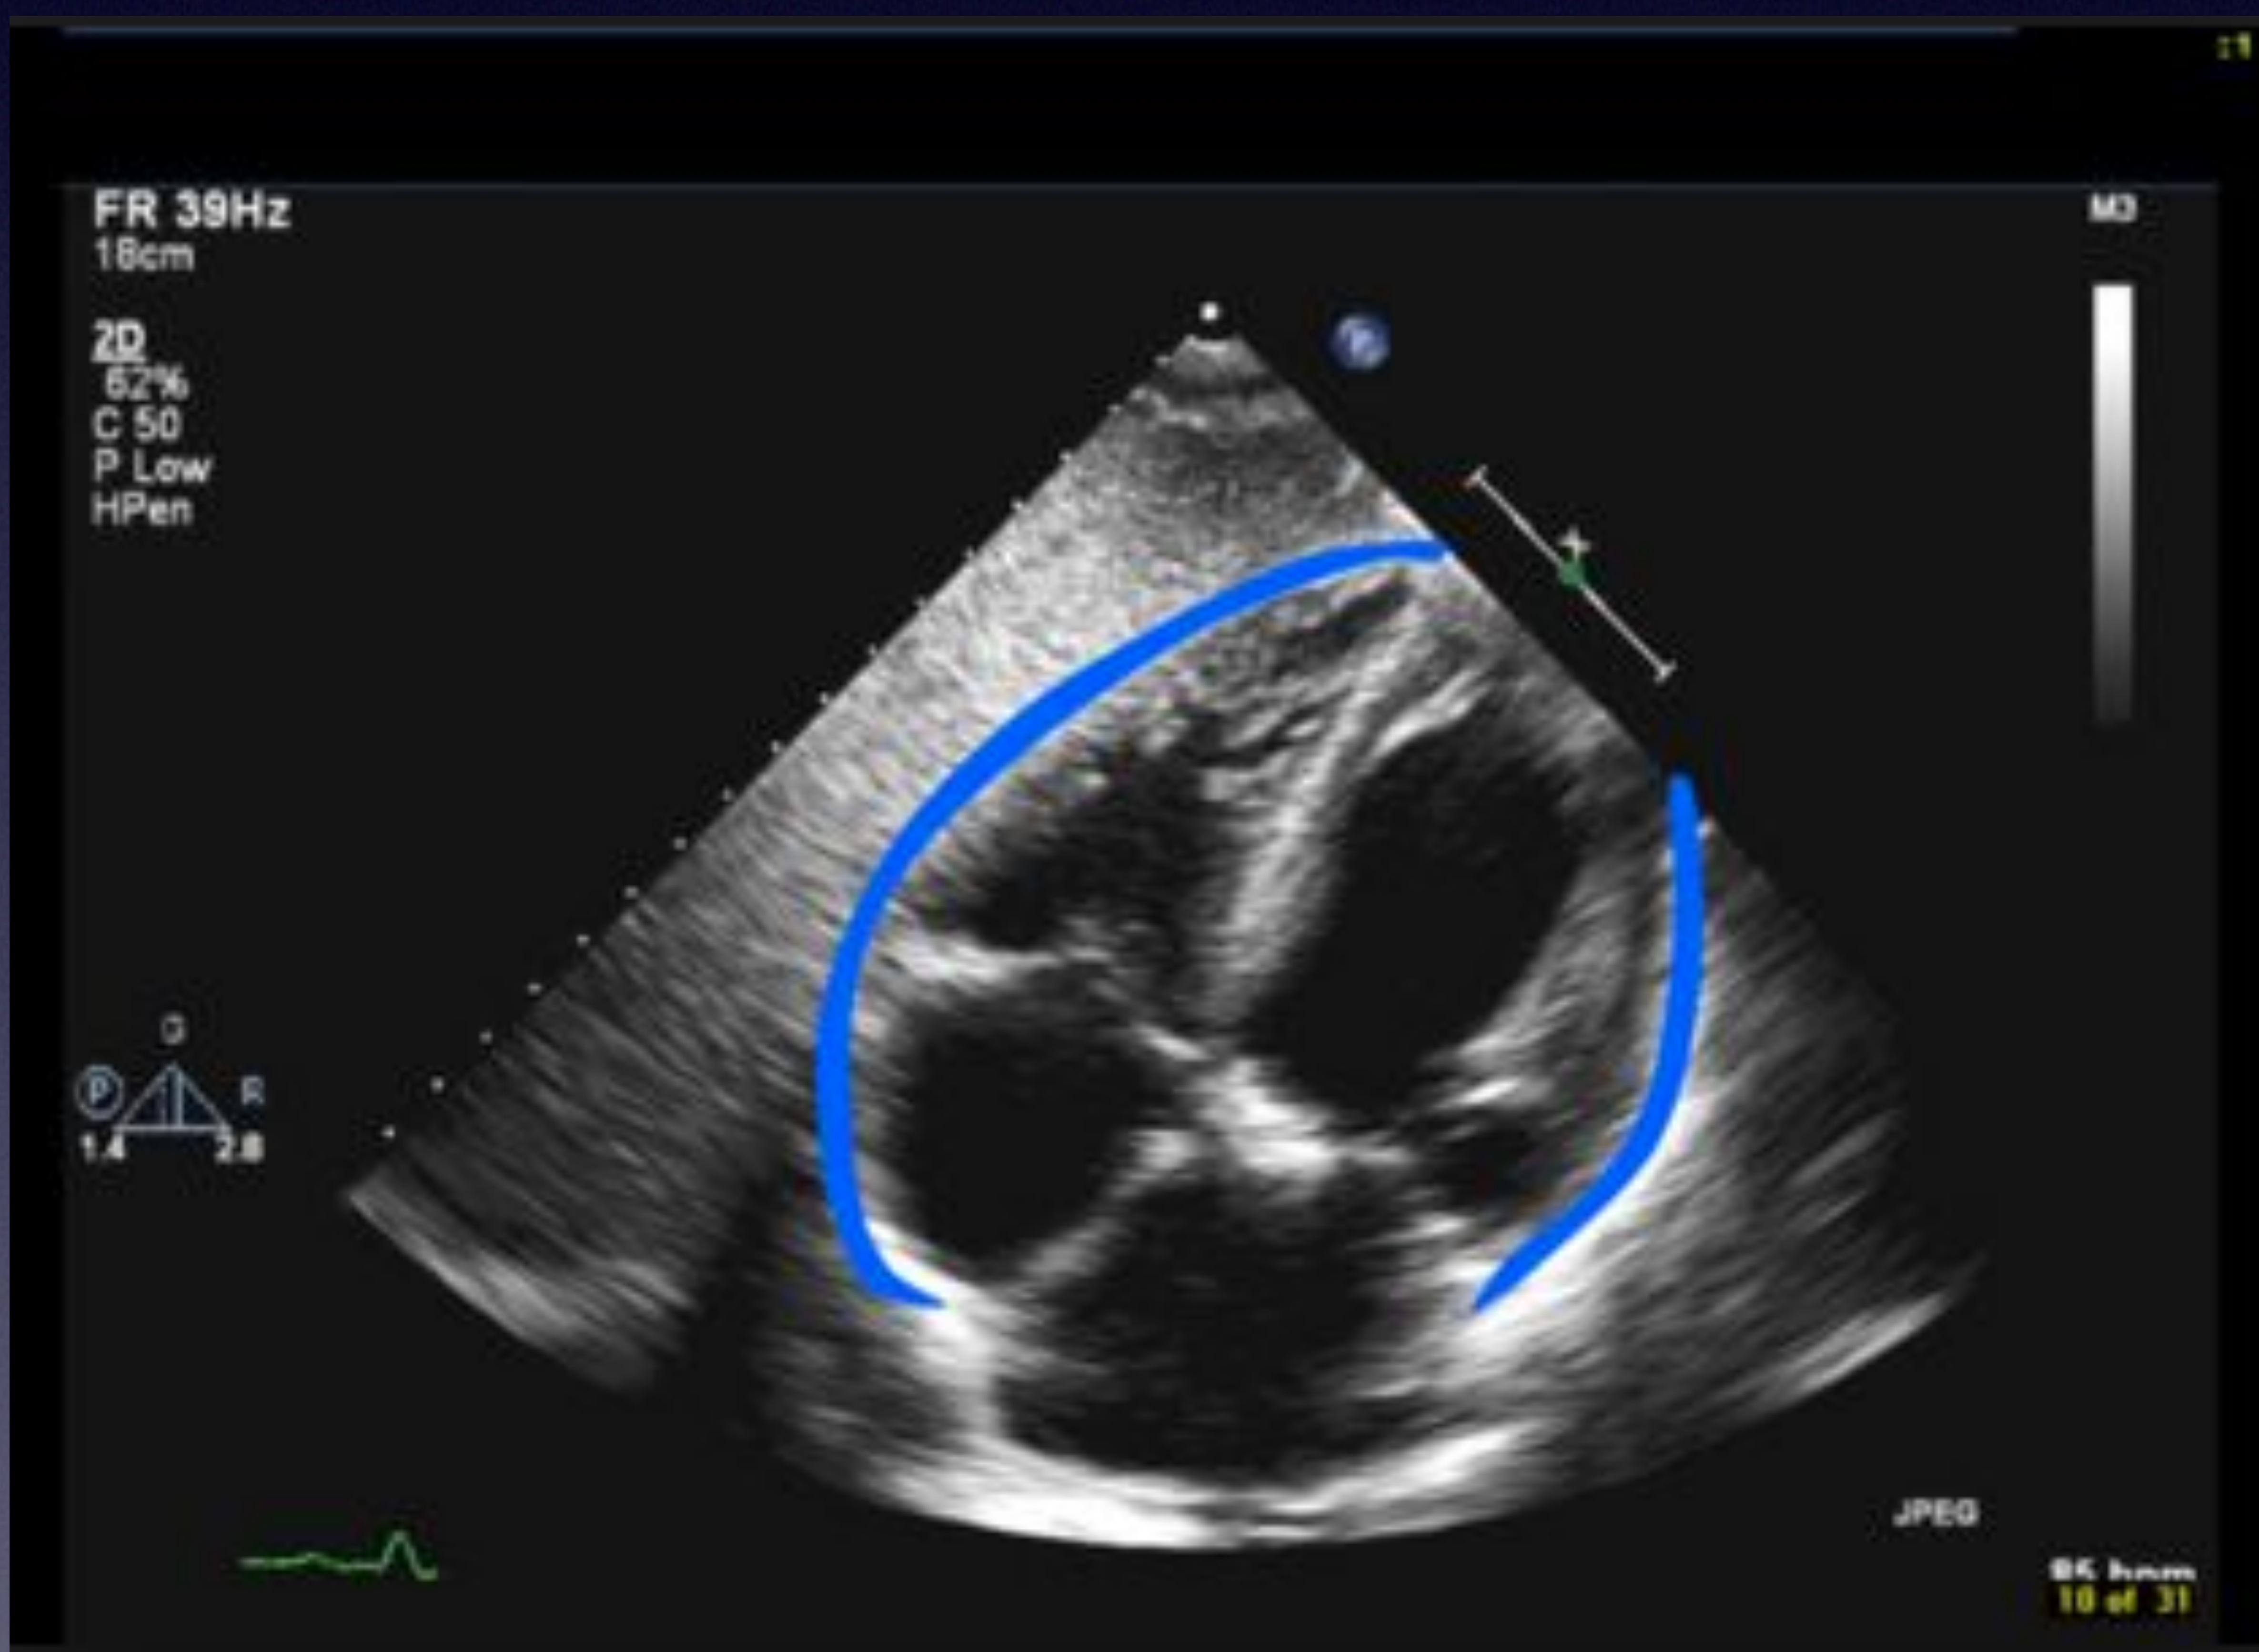

Pericardial Scan

Pericardial space showing fluid accumulation (effusion).

Subcostal 4 Chamber view with Effusion & RA Collapse.